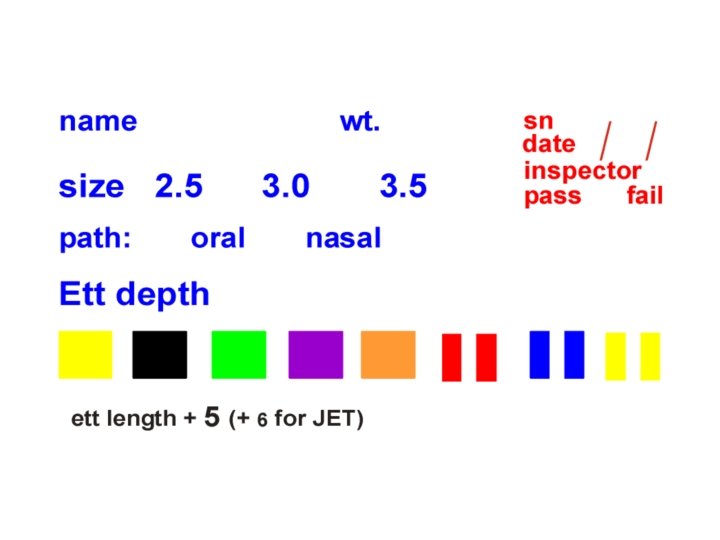

Equipment and Supplies l Equipment should be clean, protected from contamination. Wear gloves l Sterile disposable endotracheal tubes with uniform diameters preferred. Size is based on gestational age. l Stylette is optional ETT Size (mm) Wt. Gest. (kg) (wks) 2. 5 < 1 <28 3. 0 1 – 2 28 -34 3. 5 2 - 3 34 -38 © 2000 AAP/AHA

Predicted Tube Location in Trachea Tip-to-lip measurement Depth of insertion Weight (kg) (cm from upper lip) . 50. 75 6 6. 5 1* 2 3 4 7 8 9 10 © 2000 AAP/AHA